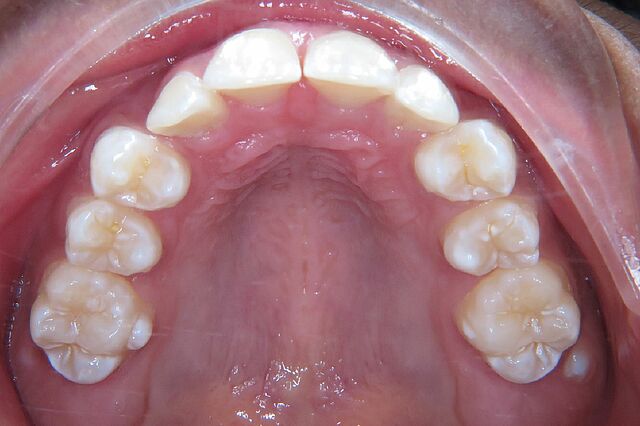

Blessy hatte einen Engstand und wurde 17 Monate mit einer festsitzenden Zahnspange behandelt.

• Engstand

Vorher Nachher Fotos

Blessy`s Zahnspange Vorher 1

Blessy`s Zahnspange Nacher 1